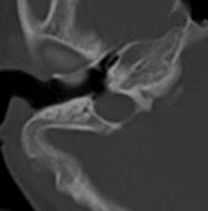

КТ. Правый мостомозжечковый угол. Расширенная яремная вена выбухает в среднее ухо.

Неприятный пульсирующий шум в ухе является нередкой жалобой пациентов. При МРТ головного мозга, обычно, не удается выявить патологию. Тем не менее, есть несколько венозных аномалий, которые могут вызывать этот симптом. Высокое расположение луковицы яремной вены или дивертикул яремной вены приводят к истончению сигмовидной пластинки очень близкому расположению вены к среднему уху. Встречаются аномалии строения черепа, когда пластинка и вовсе отсутствует и тогда яремная вена выбухает (“вскрывающийся” луковица яремной вены) в полость среднего уха. При МРТ головного мозга или КТ выявляется “образование” в ретротимпаническом пространстве.

При МРТ в СПб наибольшую сложность мы видим в дифференциальной диагностике такого редкого варианта строения яремной вены с опухолью. Опасность состоит в ошибочной биопсии с фатальным кровотечением. Надо сказать, что яремные вены в норме часто несимметричны, типично расширение с одной стороны и расположение может быть высоким, вплоть до внутреннего слухового прохода. Кроме аномального расположения луковицы яремной вены, пульсирующий шум во внутреннем ухе может быть связан с опухолью югулярного гломуса, одного из вариантов хемодектом. При опухоли югулярного гломуса опухоль располагается большей частью в яремном отверстии, но также распространяется на клетки височной кости и Гальвезиев канал. Таким образом, происходит разрушение нижней стенки височной кости с переходом в среднее ухо.